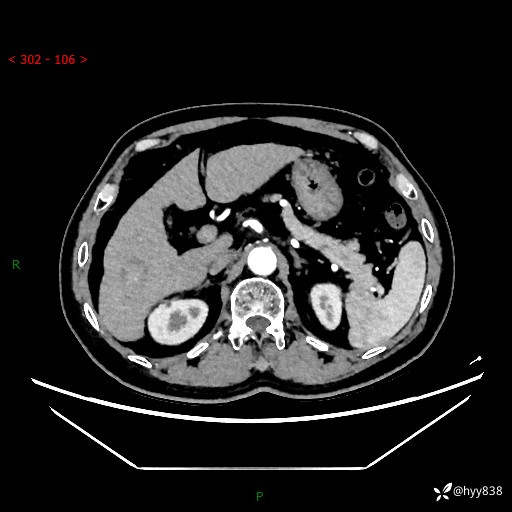

静脉期